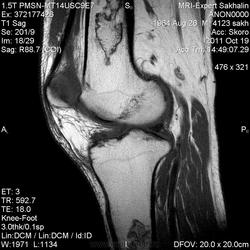

Мужчина с жалобами на боль в коленном суставе.Пришел сразу к нам по направлению врача с подозрением на ДОА, подагрический артрит.Рентгенограмм нет.

- В ранней стадии заболевания - отек (гипоинтенсивный на Т1-взвешенном изображении и гиперинтенсивный на Т2-взвешенном изображении)

- Позднее отграничение вдоль периферии пораженной кости (гипоинтенсивное на Т1 - взвешенном изображении; на Т2-взвешенном изображении - гиперинтенсивная линия по направлению к зоне некроза, соответствует грануляционной ткани)

- Гипоинтенсивная линия по направлению к здоровой кости (склероз, фиброз): признак двойной линии

- Накопление контрастного вещества периферической зоной

- При застарелых инфарктах кости интенсивность сигнала зоны некроза эквивалентна жировой ткани

- Периферическая зона типично извилистая, напоминает гирлянду.

а, b Инфаркт зрелого костного мозга. (а) Сагиттальная протонная плотно-взвешенная МРТ с подавлением МР-сигнала от жировой ткани. Изображение демонстрирует гирляндовидный склеротический край и центральный участок с сигналом жирового костного мозга. Множественные некротические зоны расположены преимущественно в метадиафизальной области, однако несколько находятся непосредственно рядом с суставом, в связи с чем имеется риск уплощения суставных поверхностей;